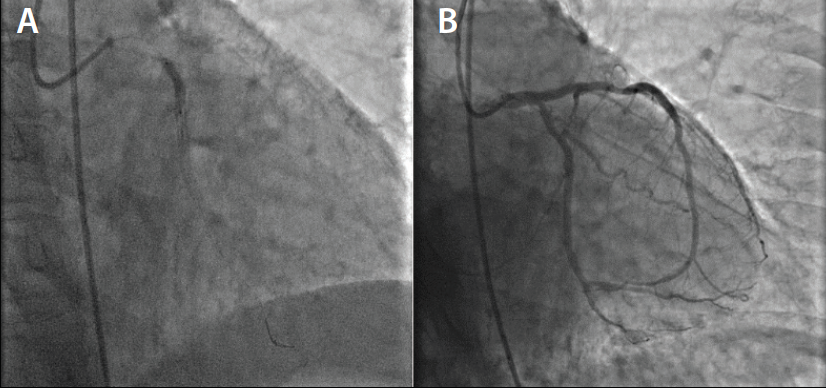

An 88-year-old man presented with cardiac symptoms including intrascapular discomfort that may be an anginal variant, dyspnea with exertion, obstructive sleep apnea, and easy fatigability. His body mass index was 36 kg/m2. He also reported episodes of shortness of breath. The patient’s thallium stress test and echocardiographic findings were normal. He was previously seen by an orthopedic surgeon for leg pain. Duplex examination showed bilateral common femoral artery velocity reduction of 0.65 cm on the right and 0.64 cm on the left; the superficial femoral artery reduction was 0.39 cm on the right and 0.51 cm on the left; and the popliteal artery reduction was 0.33 cm on the right and 0.46 cm on the left side. Diagnostic angiographic findings demonstrated severe proximal, mid, and distal LAD arterial disease (Figure 1), as well as obtuse marginal disease. The patient was a poor candidate for surgical revascularization.

A right radial approach using a 7-F Glidesheath™ Slender device (Terumo Interventional Systems) was selected, and heparin was administered throughout the procedure. A 7-F XB LAD guide catheter was engaged after poor mapping of the first guide, followed by a 0.014-cm BMW guidewire. Balloon angioplasty of the proximal LAD was performed with a 2.5-mm balloon. A 4- X 24-mm EluNIR™ stent was deployed in the proximal LAD. The second stent, a 3.5- X 20-mm EluNIR™, was placed in the mid-LAD with the assistance of a GuideLiner® device (Teleflex). The very distal LAD artery lesion requires predilatation with a 2-mm balloon before deployment of the third stent, a 2.5- X 24-mm EluNIR™. A 3.5-mm noncompliant balloon was used to “touch up” the middle of the stents. The procedure concluded with no complications (Figure 2).

Before the procedure, the patient had 90% to 95% proximal LAD stenosis and 0% stenosis postintervention. Findings also included extreme mid-LAD calcification (50%–70%) preprocedure and 0% calcification postintervention. The distal LAD stenosis was 95% before the procedure and 0% after stenting. However, there was approximately 60% to 70% distal LAD artery disease just above the wraparound portion, which was not treated. Fortunately, the diagonal branch that was located at the proximal lesion of the LAD was not placed in a stent jail.